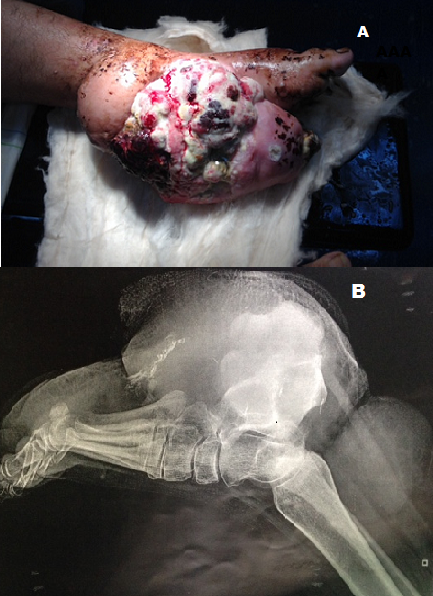

L’hémangiopericytome est une tumeur vasculaire rare classée comme sarcome des tissus mous, elle peut être bénigne ou maligne, elle prend naissance au niveau des péricytes qui sont des cellules localisées au niveau de la lame basale de l’endothélium des capillaires ce qui explique son caractère ubiquitaire. Leur traitement de référence est la chirurgie souvent complétée d’une radiothérapie. Nous rapportons un cas d’un énorme hémangiopericytome malin du pied chez une patiente de 28 ans qui nous a été adressé pour une tumeur du pied gauche nécrosée est infectée avec une biopsie qui a été réalisée revenant en faveur d’un hémangiopericytome le bilan d’extension comportant une scintigraphie osseuse et un scanner thoraco-abdomino-pelvien n’a pas objectivé de localisation secondaire Vu la taille de la tumeur et son caractère nécrosé et infectée un traitement chirurgical radical par une amputation transtibiale a été décidé après le consentement de la patiente.